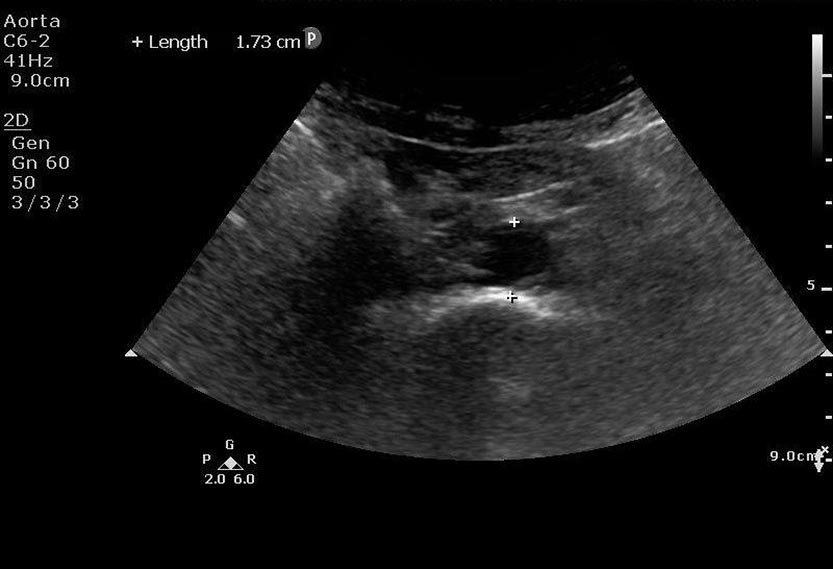

This is a 53 year old female who presents with altered mental status. She is found to have sepsis. Her urinalysis is marginally positive for infection. She is not fluid responsive and does not respond to pressor support. Hydronephrosis is discovered on bedside ultrasound resulting in urology consultation and operative management for source control.

distal aorta.jpg